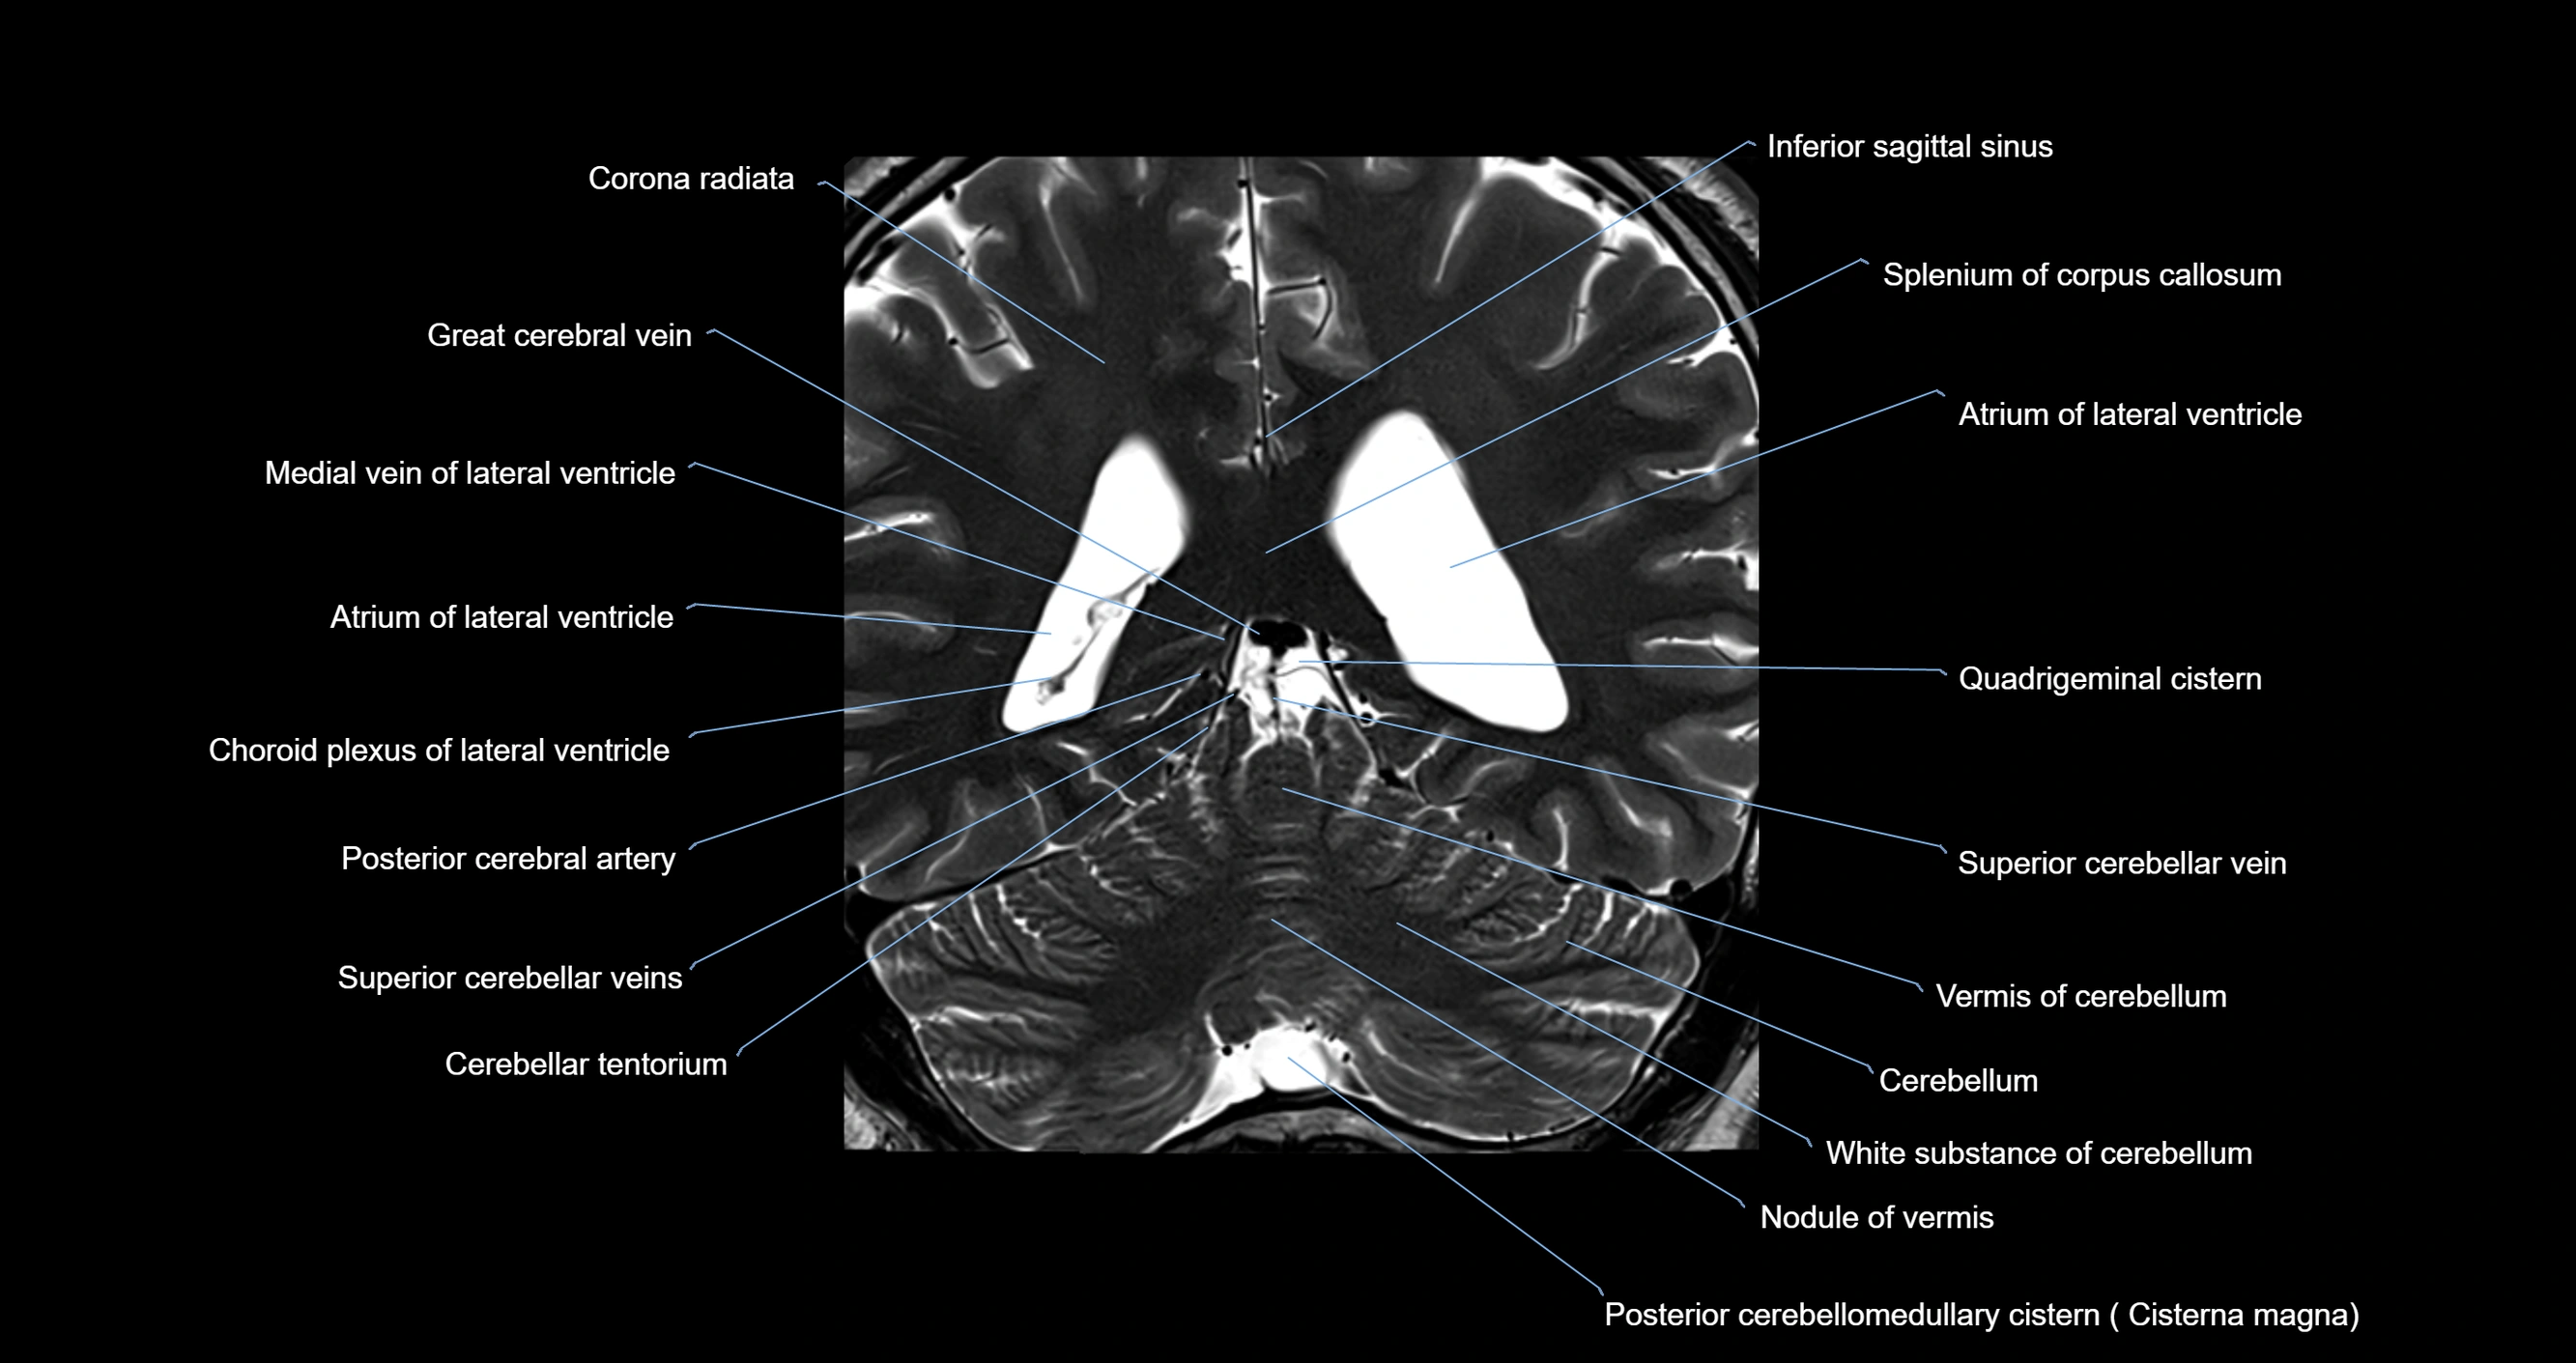

- Atrium of lateral ventricle

- Cerebellum

- Cisterna magna

- Corona radiata

- Great cerebral vein

- Inferior sagittal sinus

- Medial vein of lateral ventricle

- Nodule of vermis

- Posterior cerebellomedullary cistern (cisterna magna)

- Quadrigeminal cistern

- Splenium of corpus callosum

- Superior cerebellar vein

- Vermis of cerebellum

- White substance of cerebellum